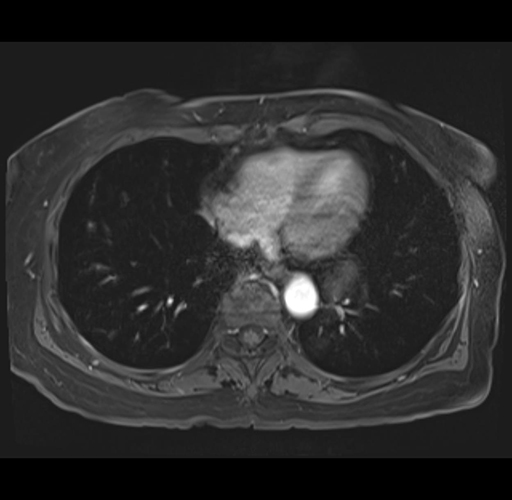

MRI T1